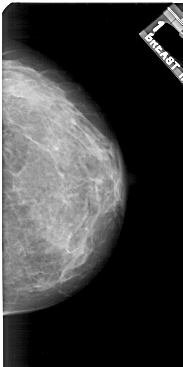

A_1921_1.RIGHT_CC

RIGHT_CC LINES 5131 PIXELS_PER_LINE 2551 BITS_PER_PIXEL 12 RESOLUTION 43.5 NON_OVERLAY